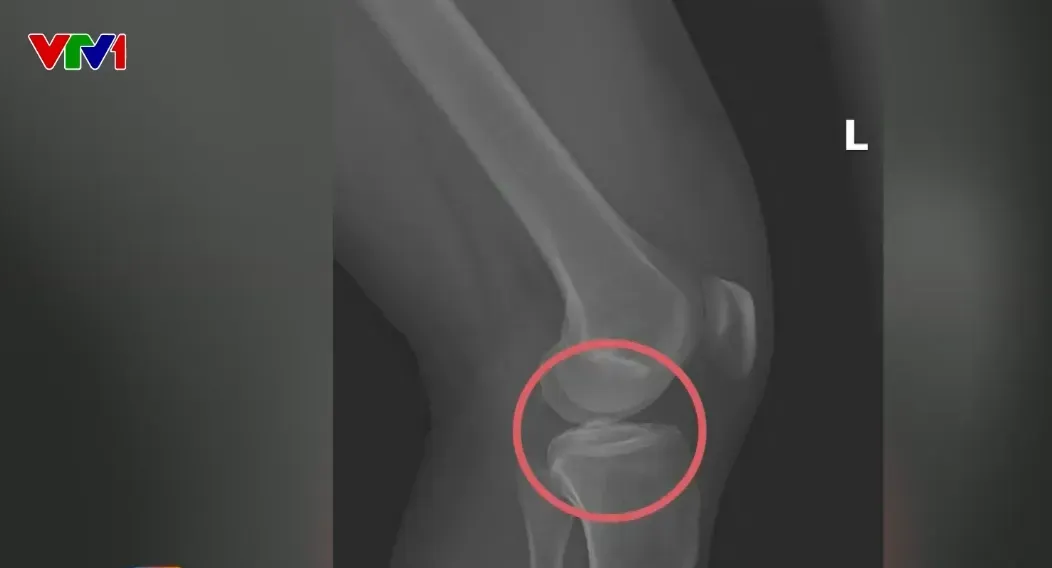

Hình ảnh chụp X-quang một số tổn thương xương do chính đối tượng cầm đầu gây thương tích.

Một sự việc gây sốc cho nhiều người vừa được làm sáng tỏ khi cơ quan điều tra đã triệt phá đường dây trục lợi bảo hiểm nhân thọ với thủ đoạn gây thương tích giả, trong đó các đối tượng tự dùng vật cứng đục vỡ xương để nhận bồi thường. Số tiền chiếm đoạt được xác định lên đến hàng tỷ đồng từ nhiều công ty bảo hiểm khác nhau. Những thông tin này lập tức gây tranh luận mạnh trên mạng xã hội. Một số nghi phạm đã bị bắt giữ để tiếp tục làm rõ vai trò và phương thức hoạt động.